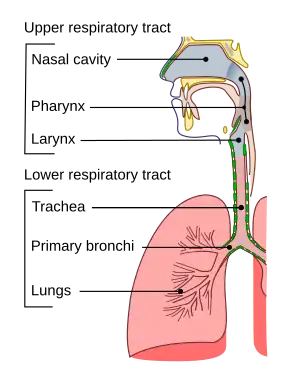

Respiratory tract

The lungs as main part of respiratory tract

The lower respiratory tract is part of the respiratory system, and consists of the trachea and the structures below this including the lungs.[32] The trachea receives air from the pharynx and travels down to a place where it splits (the carina) into a right and left primary bronchus. These supply air to the right and left lungs, splitting progressively into the secondary and tertiary bronchi for the lobes of the lungs, and into smaller and smaller bronchioles until they become the respiratory bronchioles. These in turn supply air through alveolar ducts into the alveoli, where the exchange of gases take place.[32] Oxygen breathed in, diffuses through the walls of the alveoli into the enveloping capillaries and into the circulation,[20] and carbon dioxide diffuses from the blood into the lungs to be breathed out.